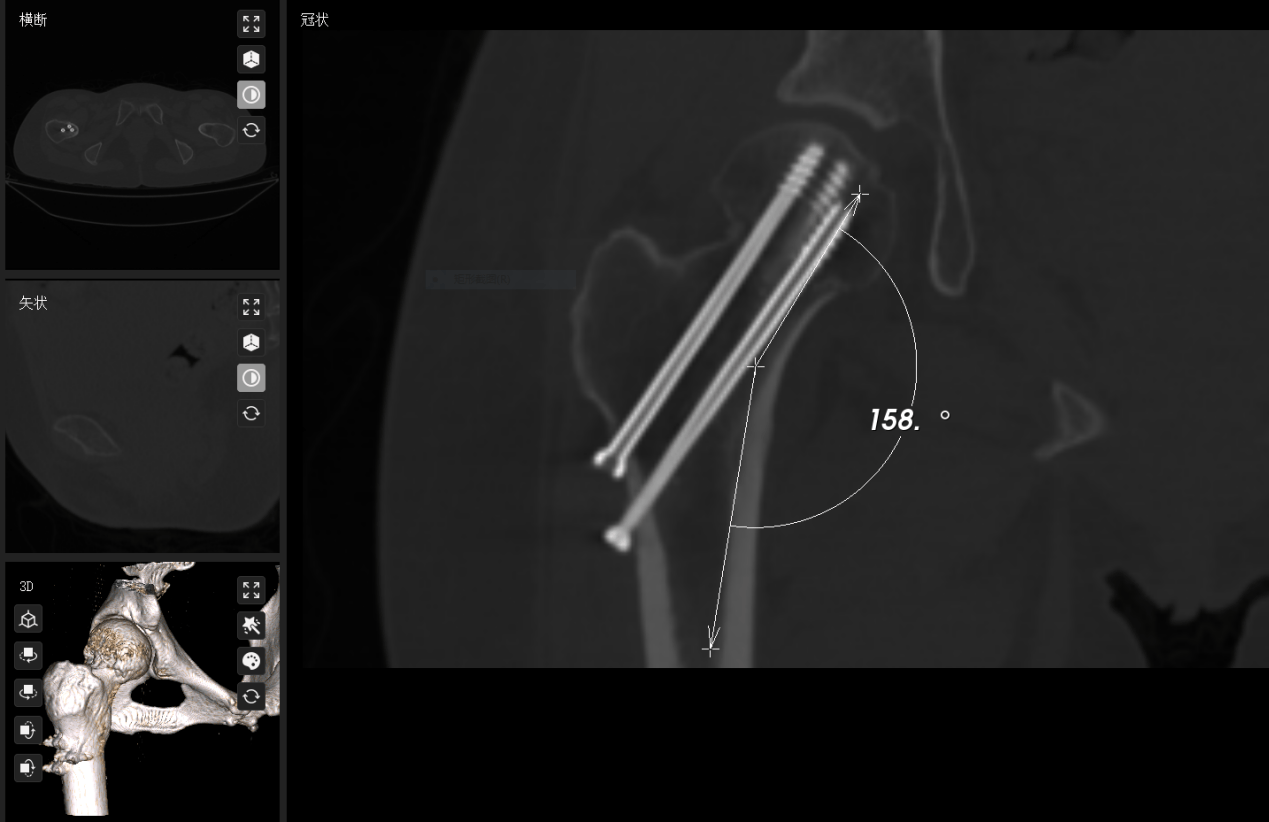

2. 机器人赋能微创固定: 利用先进的骨科机器人及数字化导航技术,叶博士团队实施了空心螺钉内固定术。

技术亮点:

亚毫米级精度(0.8mm): 将螺钉置入精度提升至亚毫米级,显著优于传统手法 ;

1. 急诊精准复位: 团队立即采用Leadbetter法进行闭合复位,在C臂机严密透视下,严格依据Garden指数,确保复位达到解剖标准,为后续微创固定打下完美基础。

4. 研究证实,复位偏差>2mm会使坏死风险骤增,而精准复位使其归入低风险。